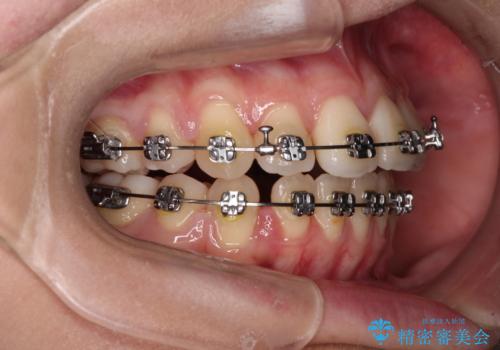

- メタルブラケット

- 1年6ヶ月

- 10-30回

舌の突出癖によるオープンバイトになっていたため、インビザラインによるマウスピース矯正をおすすめしましたが、自己管理の自信がないとのことで、ワイヤー装置による矯正治療を行うこととしました。